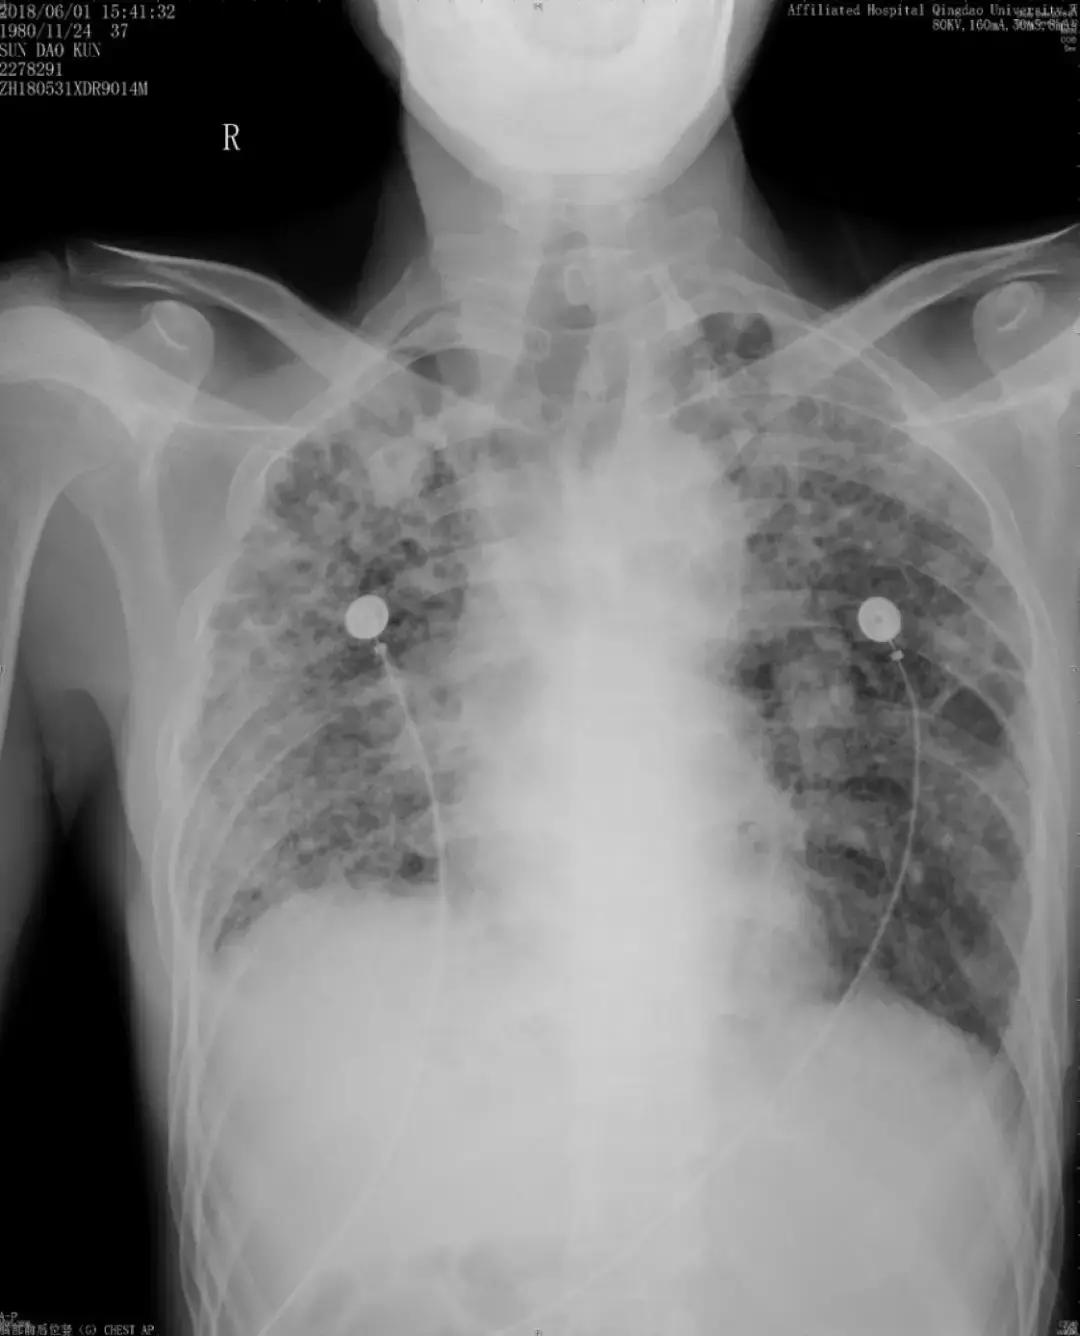

随访:活动性呼吸困难逐渐加重,出现了气胸

由于儿子反复治疗的花销已经很大了,这位患者诊断后没有特别治疗,曾去过多家医院,考虑过肺移植,但由于是遗传性疾病只好作罢。随后在我院随访,呼吸困难逐渐加重,间质改变越来越严重,原来是上肺比较明显,后来下肺病变也加重了,再后来右上肺出现大泡,最后出现气胸,反复住院,这个患者后来再也没有来了……

胸部正位片(2018-06-01):最后一次